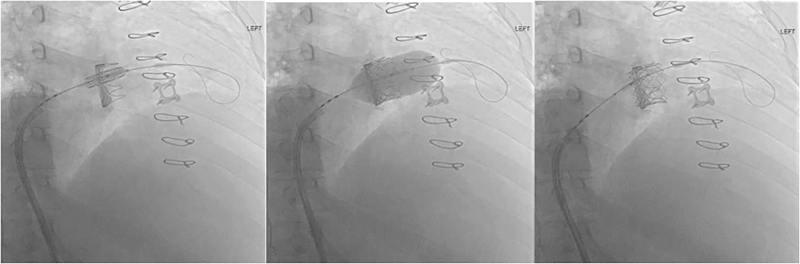

Access was obtained in the right femoral vein using a 6F sheath. The sheath was then upsized to 16F. A pigtail catheter was advanced through the venous sheath to the tricuspid valve and into the right ventricular cavity over a J-wire, which was then exchanged for a stiff wire. The 29 mm Edwards Sapien S3 valve was placed across the bioprosthetic tricuspid valve, and its position was confirmed with fluoroscopy (Figure 2). The transcatheter valve balloon was manually inflated, and the valve was deployed. The wire was removed from the valve, and TEE confirmed no paravalvular or central regurgitation. Subsequently, the femoral venous delivery sheath was removed, and the Perclose suture was deployed to close the venotomy.

Figure 2

Figure 2. Fluoroscopic transcatheter TViV placement and deployment of the Edward 3 Sapien valve in the tricuspid position.